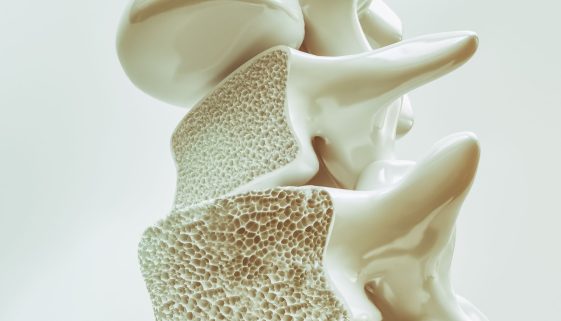

تُعد جراحة عظام الأطفال من المجالات الحساسة والمهمة التي تتطلب اهتمامًا خاصًا من أولياء الأمور والمعالجين الطبيين. إذا كنت تفكر في كيفية الاعتناء بصحة طفلك بعد إجراء جراحة العظام، فهذا المقال يقدم رؤى قيمة ونصائح تثقيفية حول كيفية التعامل مع هذا الأمر بأفضل السبل الممكنة. ماهي جراحة عظام الأطفال؟ تتعلق […]